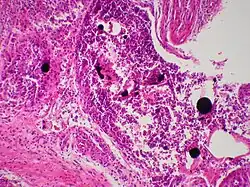

Cutaneous mercury granuloma is a rare disorder caused by the introduction of elemental Hg into skin.

Mercury granulomas is the result of mercury exposure, a skin condition characterized by foreign-body giant cell reaction.[1]: 46